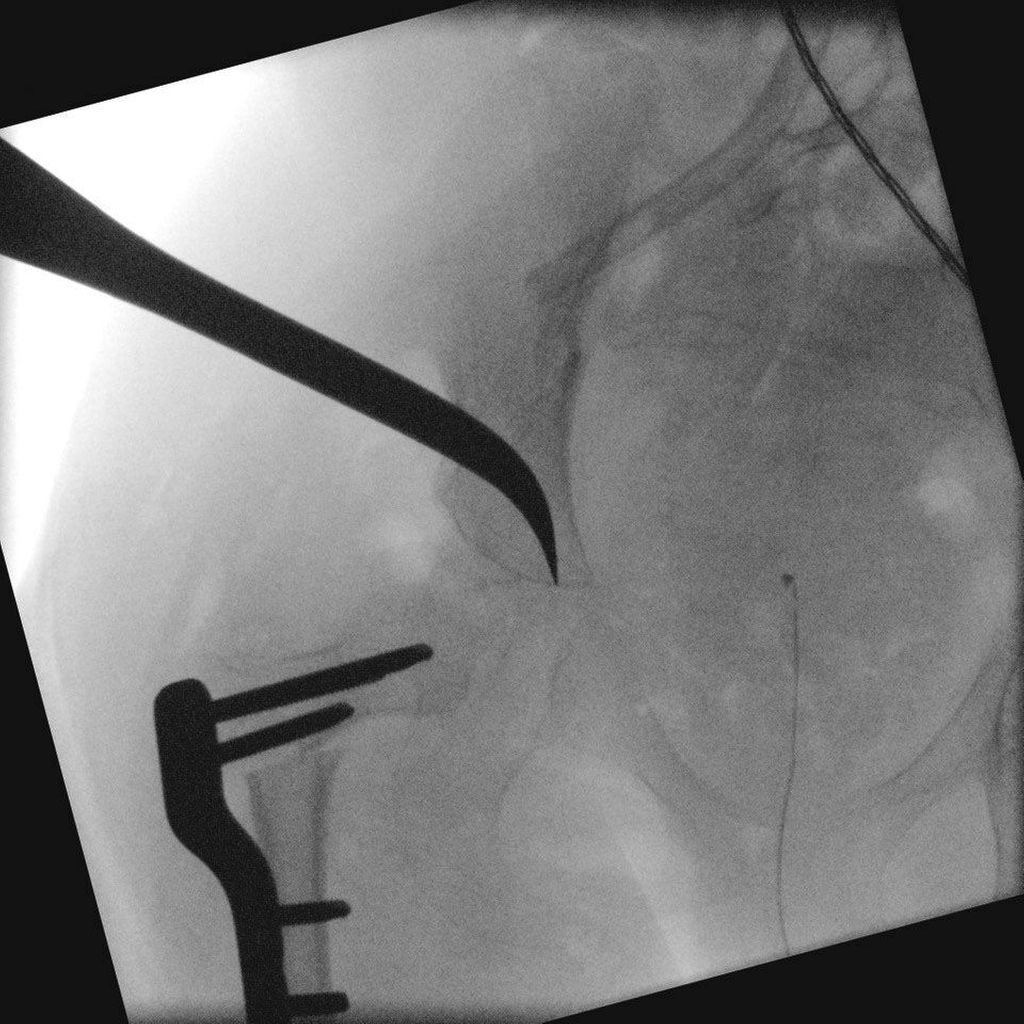

Abb. 2: Dega-Beckenosteotomie (Pemberton-Meißel wird in Richtung Y-Fuge vorgetrieben)

Dega-Osteotomie

Die von den meisten Autoren empfohlene und am häufigsten durchgeführte Osteotomie bei Kindern mit Hüftfdezentrierung im Rahmen einer ICP ist die Dega-Beckenosteotomie. Voraussetzung für diese Osteotomie ist eine offene Y-Fuge. Hierbei wird die Lamina externa des Iliums unter Aussparung des posteromedialen Anteils und der Incisura ischiadica mit einem gebogenen Meißel, z.B. einem Pemberton-Meißel, durchtrennt. Anschließend wird das Pfannendach nach kaudal und lateral mobilisiert und ein trikortikaler Knochenspan, welcher zuvor bei der Femurosteotomie entnommen wurde, zur Sicherung eingebolzt. Die Osteotomie nutzt dabei die Y-Fuge als Drehpunkt. Durch das feste Verklemmen des Spans ist in aller Regel eine zusätzliche Osteosynthese nicht notwendig.4